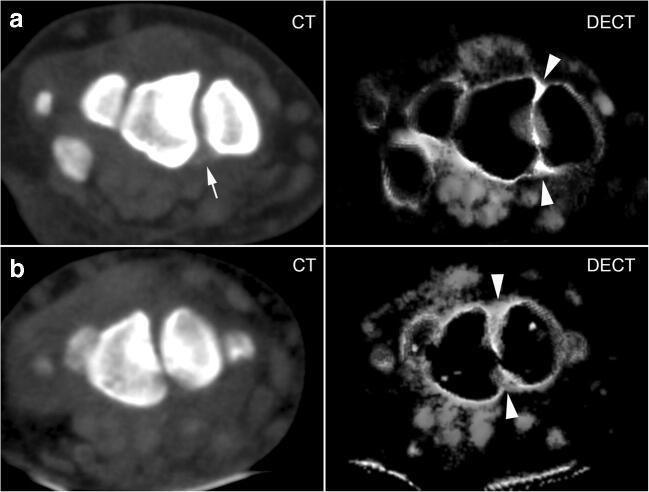

This retrospective study included 28 patients (18 with CPPD, 10 controls) who underwent DECT of the wrist. Collagen density maps were reconstructed from the DECT datasets and used to measure densities in regions of interest (ROIs) placed in the scapholunate (SL) ligament (dorsal, palmar, proximal), lunotriquetral (LT) ligament, and extensor carpi radialis (ECR) tendon, (n = 260 measurements). The presence of calcifications on standard CT images in these regions was assessed by a blinded reader. Densities were compared with nonparametric tests, and linear regression analysis was performed to investigate the impact of age, sex, and CT- detected calcium deposition on collagen density.

Collagen density in the SL ligament was significantly higher in CPPD patients than in controls (overall mean: 265.4 ± 32.1 HU vs. 196.3 ± 33.8 HU; p < 0.001). In the ECR tendon, collagen densities did not differ significantly (p = 0.672): 161.3 ± 20.1 HU in CPPD vs. 163.6 ± 12.0 HU in controls. Regression analysis showed that diagnosis, but not age or calcification, had a significant impact on collagen density.

本回顾性研究纳入了 28 例患者(18 例 CPPD,10 例对照组),均行腕部 DECT 检查。从 DECT 数据集中重建胶原密度图,并用于测量放置在舟月(SL)韧带(背侧、掌侧、近侧)、月三角(LT)韧带和桡侧腕伸肌(ECR)肌腱的感兴趣区(ROI)中的密度(n=260 个测量值)。由一位盲法读者评估这些区域标准 CT 图像上的钙化情况。使用非参数检验比较密度,进行线性回归分析以研究年龄、性别和 CT 检测到的钙沉积对胶原密度的影响。

CPPD 患者的 SL 韧带胶原密度明显高于对照组(总体平均值:265.4±32.1 HU 比 196.3±33.8 HU;p<0.001)。ECR 肌腱的胶原密度无显著差异(p=0.672):CPPD 患者为 161.3±20.1 HU,对照组为 163.6±12.0 HU。回归分析显示,诊断而非年龄或钙化对胶原密度有显著影响。